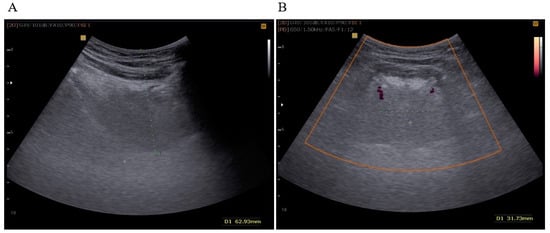

After examination of the oral cavity, the tongue USG examination was conducted with a Samsung SonoAce X8 device (convex probe 2–8 MHz). During the assessment, patients were instructed to maintain a neutral, relaxed position of the tongue. TBT was measured in the sagittal plane and DLA using the Power Doppler (PD) mode in the coronal plane (Figure 1). All examinations were performed by an experienced examiner, who is a specialist in pulmonology (M.S.), trained in performing USG of the supradiaphragmatic spaces. These procedures were carried out under the supervision of a somnologist (K.Z.). In agreement with the findings presented by Liao et al. (2016), we concur that the ultrasound methodology employed in this study is comfortable, non-invasive, and efficient for diagnosing severe OSAS [].

Figure 1. (A) TBT measured in the sagittal plane (green dots); (B) DLA measured in the coronal plane in the PD (Power Doppler) mode (green dots).

TBT was expressed as the distance in millimeters between the lowest point in the convexity of the image and the highest echo point of the mucosa covering the tongue. DLA was expressed in millimeters as the distance between the Doppler image of the right and left lingual arteries at the most proximal point delineated by mandibular shadows. Initially, we set a cut-off value of TBT ≥ 60 mm and DLA ≥ 30 mm, as described in a previously published study of an Asian population by Liao et al. [].